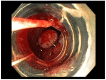

Gastric and esophageal tumors are diverse neoplasms that involve mucosal and submucosal tissue layers and include squamous cell carcinomas, adenocarcinomas, spindle cell neoplasms, neuroendocrine tumors, marginal B cell lymphomas, along with less common tumors. The worldwide burden of esophageal and gastric malignancies is significant, with esophageal and gastric cancer representing the ninth and fifth most common cancers, respectively. The approach to diagnosis and staging of these lesions is multimodal and includes a combination of gastrointestinal endoscopy, endoscopic ultrasound, and cross-sectional imaging. Likewise, therapy is multidisciplinary and combines therapeutic endoscopy, surgery, radiotherapy, and systemic chemotherapeutic tools. Future directions for diagnosis of esophageal and gastric malignancies are evolving rapidly and will involve advances in endoscopic and endosonographic techniques including tethered capsules, optical coherence tomography, along with targeted cytologic and serological analyses.